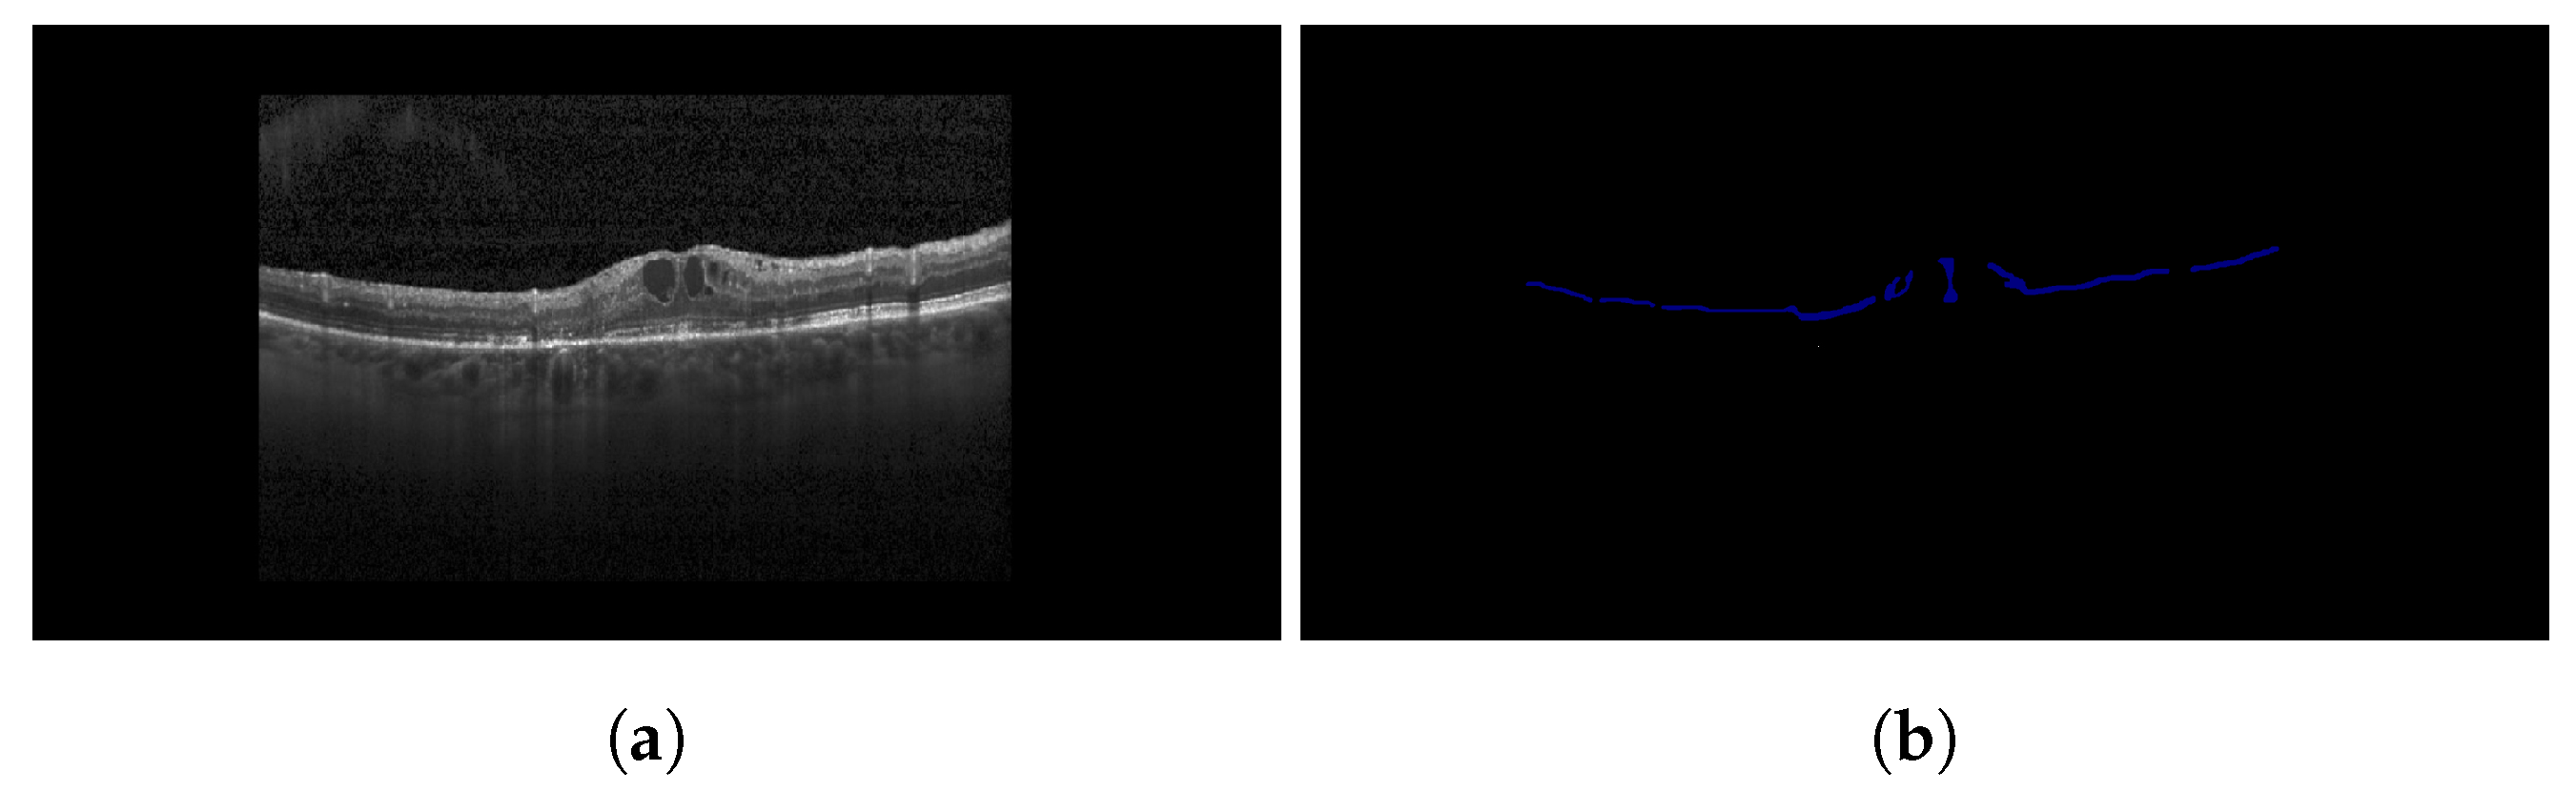

2.2. Hyperreflective Foci

3.1.2. Hyperreflective Focii (HRF)

4.3.2. HRF